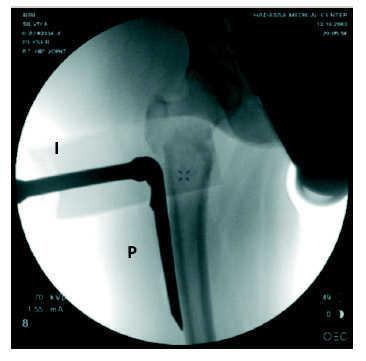

Figura 7

Se realiza un control por imagen en proyección AP para confirmar la posición de la placa. Está bien colocada cuando se encuentra por debajo del trocánter mayor. En esta imagen escópica se muestran la placa (P) y el introductor (I).